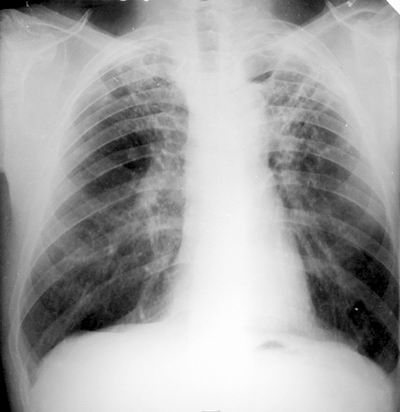

La tuberculosis (TB) es una enfermedad infecciosa causada por una bacteria (un bacilo) denominada Mycobacterium tuberculosis (que fue descubierta en 1882 por Roberto Koch), que una vez que entra al cuerpo circula por la sangre y el sistema linfático y suele afectar a los pulmones, aunque también puede afectar a otras partes de tu cuerpo.